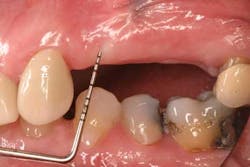

Mucograft® is an example of a xenograft material that has been used in lieu of autogenous grafts to increase keratinized tissue around dental implants (21). Made of porcine collagen, this material has a compact outer layer that can be left exposed to the oral environment and a spongy inner layer that facilitates a blood clot and promotes angiogenesis. A major advantage in using this material for increasing keratinized tissue around dental implants is that it can be used in challenging areas with little to no attached soft tissue because primary closure over this graft material is not needed and it can be left exposed (Figs. 3a-3c).

Fig. 3a: Edentulous Nos. 12 and 13 slated for implant therapy with a limited amount of keratinized tissue.